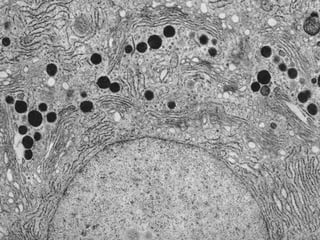

Este documento presenta imágenes microscópicas de diferentes tipos de tejidos y estructuras celulares teñidas con varios métodos histológicos. Incluye fotografías que muestran fibras de colágeno, elásticas y reticulares en diversos órganos, así como membranas basales y células especializadas de órganos como riñones, glándulas mamarias y próstata. El propósito es demostrar la aplicación de técnicas histológicas para visualizar componentes celulares y tej